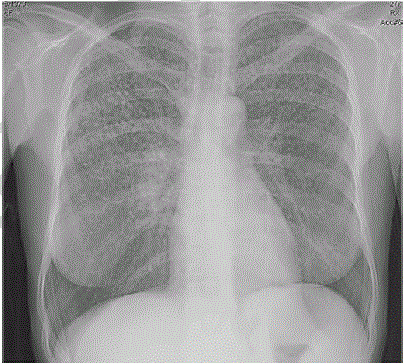

Uma paciente de 45 anos de idade compareceu, acompanhada pela filha, a consulta ambulatorial. Queixa-se de perda de peso (em tomo de 4 kg nos últimos seis meses), febre vespertina e fadiga há mais de 20 dias. Observou que tem trabalhado muito, tem uma fadiga crônica e acha que iniciou os sintomas após exposição à chuva e a vento frio quando voltava do trabalho para casa. Ela informa que é etilista social e tabagista (15 cigarros/dia), e apresentou alguns exames laboratoriais como hemograma, eletrólitos, função hepática e renal normais. Os raios X de tórax estão representados na imagem a seguir. O resultado do PPD e o lavado brônquico são negativos.

A imagem dos raios X de tórax coloca a tuberculose como diagnóstico diferencial.